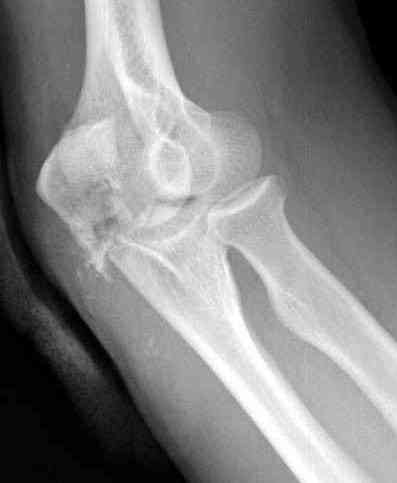

При самом большом к Вам уважении, Сергей Анатольевич, не соглашусь. У меня, после того, как добавили "прямой" снимок, сомнений не осталось. Венечный сломан наверняка. Но чтобы судить, насколько это критично для стабильности, нужно иметь строго боковую проекцию. И при этом помнить, что на него крепятся медиальные связки.

Прикрепляю снимок, где обведен фрагмент, несущий на себе венечный отросток (весь он смещён с этим фрагментом или частично - без качественной боковой проекции судить сложно), и отдельно на снимке обведено "ложе", от которого он сместился.

Почему я в данном случае против Вебера (хотя обычно горячий сторонник)? Да потому, что спицам нередко не хватает жёсткости, чтобы удержать предплечье от волярного подвывиха. При таком оскольчатом переломе спицы порой просто "прогибаются" за счёт одного только натяжения проволочной петли и головка луча может уйти в волярный подвывих (может, конечно, и не уйти). Но я бы предпочёл фиксировать всё к жёсткой пластине (включая фрагмент с венечным отростком) и, по возможности, исключить послеоперационную внешнюю иммобилизацию. Накладывать на такой локоть после операции гипс -- означает обрекать его на тяжёлую контрактуру.

Головка луча, кстати, на мой взгляд цела.